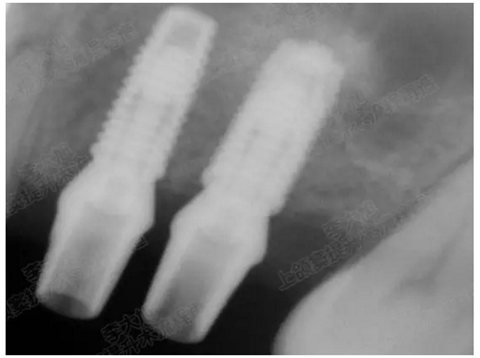

修復(fù)時根尖片

08.png